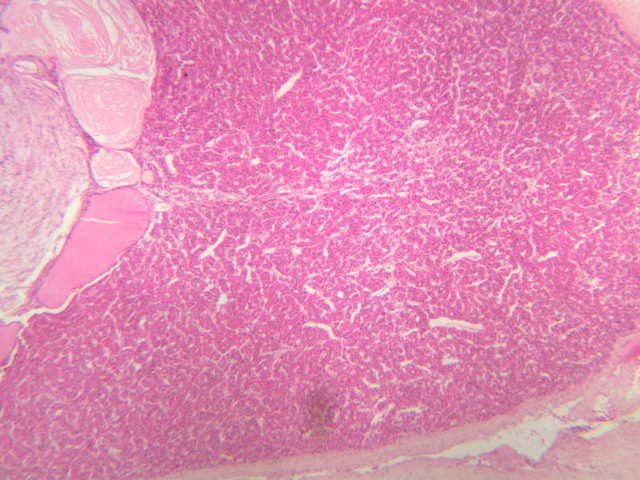

On the basis of both its architecture and embryonic origins, the pituitary gland may be subdivided into two portions: the adenohypophysis (anterior pituitary) and the neurohypophysis (posterior pituitary). (Note: the pituitary sections in your slide boxes were cut in a more or less transverse plane. As a result, a centrally located neurohypophysis is flanked by the various parts of the adenohypophysis.)

The adenohypophysis arises from oral ectoderm and forms the largest subdivision of the pituitary gland. It consists of three regions: (1) pars tuberalis, which wraps around the pituitary stalk; (2) pars distalis, which makes up most of the anterior portion of the adenohypophysis; (3) pars intermedia, which lies between the pars distalis and the pars nervosa of the neurohypophysis and is characterized by the presence of colloid-filled cysts. In H&E-stained sections, the adenohypophysis is darker than the neurohypophysis (B-63, H&E [2.5x, 10x-labeled, 20x]; B-64, aldehyde fuchsin [2.5x, 10x, 20x, 40x]; B-65, trichrome [2.5x]).

The neurohypophysis arises as an outpocketing of neuroectoderm from the floor of a portion of the brain called diencephalon. It is divisible into the pars nervosa, which forms the posterior portion of the main mass of the pituitary, and the infundibulum, or pituitary stalk. In H&E-stained sections, the neurohypophysis is distinctly eosinophilic. The adenohypophysis (anterior pituitary) has three different types of secretory cells, which are best visualized in the trichrome-stained preparation on slide B-65: (1) acidophils have a reddish staining cytoplasm, owing to the presence of secretory granules. These cells secrete growth hormone (GH) and prolactin (PRL); (2) basophils are slightly larger cells with bluish staining granules present in the cytoplasm. These cells tend to occur in small groups or clusters. Basophils are responsible for the production of thyroid stimulating hormone (TSH), adrenocorticotrophic hormone (ACTH), and the gonadotrophic hormones follicle stimulating hormone (FSH) and luteinizing hormone (LH ); (3) chromophobes or C cells are smaller cells and have only a small amount of poorly staining cytoplasm (B-63, H&E [2.5x-labeled, 10x, 20x, 40x-labeled] [2.5x, 10x, 20x, 40x-labeled]; B-65, trichrome [2.5x, 10x, 20x, 40x-labeled] [2.5x, 10x, 20x, 40x] [10x, 20x, 40x-labeled] [2.5x, 10x, 20x, 40x] [2.5x, 10x, 20x, 40x]). What is the target organ of each of the hormones produced by the adenohypophysis? Note the rich vascularity of the adenohypophysis. Can you describe the blood supply and its significance?

The neurohypophysis (posterior pituitary) (light pink in slide B-63, H&E [2.5x, 10x, 20x, 40x]; B-65, trichrome [2.5x-labeled, 10x, 20x, 40x] [2.5x-labeled, 10x, 20x, 40x]) consists in large part of the axons and axon terminals of neurosecretory cells whose cell bodies are located in the supraoptic and paraventricular nuclei of the hypothalamus. The unmyelinated axons of these cells pass through the infundibulum and end in relation to the numerous blood vessels of the pars nervosa. Dark purple granules of variable shapes and sizes are evident in the pars nervosa on slide B-64, stained with aldehyde fuscin ([2.5x, 10x, 20x, 40x-labeled] [2.5x, 10x, 20x-labeled, 40x]). These structures, which are known as Herring bodies, represent accumulations of neurosecretory material in transit from the hypothalamus to release sites in the posterior pituitary. Two neurosecretory products are associated with the posterior pituitary: oxytocin (milk letdown factor) and antidiuretic hormone (ADH or AVP, originally called vasopressin). What are the target organs of the neurohypophyseal hormones?